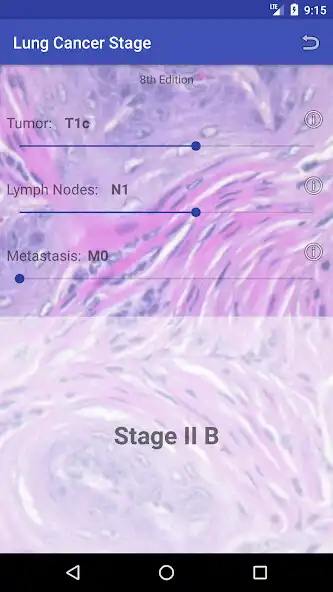

Lung cancer is the most common malignancy in the United States. The prognosis of lung cancer depends on its stage. This application calculates the stage of the tumor according to the TNM classification, where T represents the characteristics of the primary tumor, N describes the presence or absence of spread to certain lymph nodes, and M details whether the tumor has spread to other structures in the body.